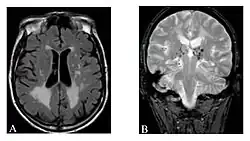

Magnetic resonance imaging (MRI) is a common form of biological data visualization used to form pictures of internal biological processes. Different settings of radiofrequency pulses and gradients result in different image appearances; these combinations are known as MRI sequences. A particularly notable subset of MRI is magnetic resonance angiography, which is a group of techniques used to image arteries and veins. MRI's imaging utility is further expanded upon by diffusion MRI and functional MRI, which can be used to capture neuronal tracts and blood flow respectively.

Diffusion MRI further relies on diffusion tensor imaging (DTI), which measures water molecule diffusion and directionality, and diffusion basis spectrum imaging (DBSI), which extracts multiple anisotropic and isotropic diffusion tensors.[39][40] Functional MRI relies on blood-oxygen-level dependent (BOLD) contrast, which measures the proportion of oxygenated hemoglobin in specific areas of the brain; this allows it to measure and model brain activity based on blood flow.[41] Further MRI techniques include saturation pulses (used to reduce motion artifacts), gradient echo (such as dynamic contrast enhancement), spin echo, and diffusion weighting (a signal contrast generation method based on differences in Brownian motion).[42][43][44]

In general, two aspects of the relaxation process are measured: the time taken for the magnetic vector to return to its resting state (also known as T1 or spin–lattice relaxation), and the time taken for the axial spin of the hydrogen protons to return to its resting state (also known as T2 or spin–spin relaxation).[47] To create a T1-weighted image, the MR signal is measured by changing the amount of time between RF pulses (also known as the time to repeat, or TR). To create a T2-weighted image, the MR signal is measured by changing the amount of time between delivering the RF pulse and receiving the RF energy signals from the hydrogen protons (also known as the time to echo, or TE). The dominant signal intensities of T1 image weighting are fluid (black due to low intensity), muscle (grey due to intermediate signal intensity), and fat (white due to high signal intensity). Fat suppression is applied to many T1 weighted sequences to suppress the brightness of the signal created by it. The dominant signal intensities of T2 image weighting are fluid (white), muscle (grey), and fat (white). T2 signals are also often emphasized or suppressed depending on what the goal of the imaging is; notable examples include fat suppression, fluid attenuation, and susceptibility weighting.

Also of note are proton density (PD) weighted images, which are generated using a long TR and a short TE. PD is useful for differentiating between fluid, hyaline cartilage and fibrocartilage, which makes it ideal for imaging joints. Outside of joint imaging it has largely been replaced by fluid attenuated inversion recovery (FLAIR), an inversion recovery sequence that removes the signal from cerebrospinal fluid.[48]